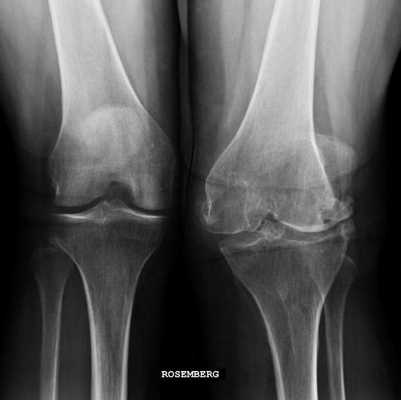

Гонартрит коленного сустава на рентгене.

Стадии артрита коленного сустава на рентгене.